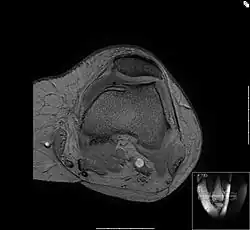

Bei dem Bild „Femoropatellararthrose“ handelt sich um ein horizontales Schnittbild durch das Kniescheibengleitlager und dem unteren Ende des Oberschenkels, den Femurkondylen. Das Bild wurde mit einem NMR-Gerät erstellt. Zu sehen sind die dünne Knorpelschicht (die Kniescheibe ist nach außen verschoben), die Kniescheibengleitrinne und die Rückfläche der Kniescheibe. Diese hat mit Knochenausziehungen, den Osteophyten, auf die geänderten Belastungsverhältnisse reagiert: Der an den Knorpel angrenzende Knochen ist verdichtet.

Am Gleitlager der Kniescheibe kommt es vielfach zu einer ungleichmäßigen Lastverteilung in diesem Gelenkabschnitt. Die Streckmuskulatur des Oberschenkels kann innerhalb kurzer Zeit (14 Tage) auf eine eingeschränkte Belastbarkeit des Knies reagieren, der körpermittig gelegene Bauch dieses Muskels (Quadriceps, der Vierköpfige) verliert schnell an Kraft mit der Folge, dass die Last auf die Kniescheibenrückfläche verlagert wird.

Der Knorpel der Kniescheibenrückfläche ist mit bis zu 7 mm die dickste Knorpelschicht im Körper. Dieser Knorpel wird nicht durchblutet, sondern nur über die Gelenkflüssigkeit ernährt. Bei dieser Dicke kann das nicht mehr durch Diffusion allein funktionieren. Hier kommt ein Walkvorgang zum Tragen: Unter Last wird Synovia (Gelenkflüssigkeit) in den Knorpel hinein- und wieder herausgedrückt. Damit ist ein genügender Austausch gegeben, solange die Auflagelast im physiologischen Bereich bleibt. Das System verträgt weder zu viel noch zu wenig Druck. Weicht dieser Druck weit genug vom Idealbereich ab, kommt es zu Ernährungsstörungen des Knorpels und später zu Verschleißerscheinungen, die auch als Chondropathia patellae bezeichnet werden. Der Knorpel degeneriert, fasert auf, wird rau: Das Gleitlager der Kniescheibe fängt an zu reiben. Man spricht nun von einer Demaskierung des Knorpels. Das erste Symptom hierbei ist der Schmerz auf der Treppe, beim Aufrichten aus der Hocke oder beim längeren Sitzen. Der Volksmund nennt diese Symptome „Theaterknie“, weil sie früher bei Menschen auftraten, die nach dem ersten Akt eines Stückes mit den Füßen scharrten.